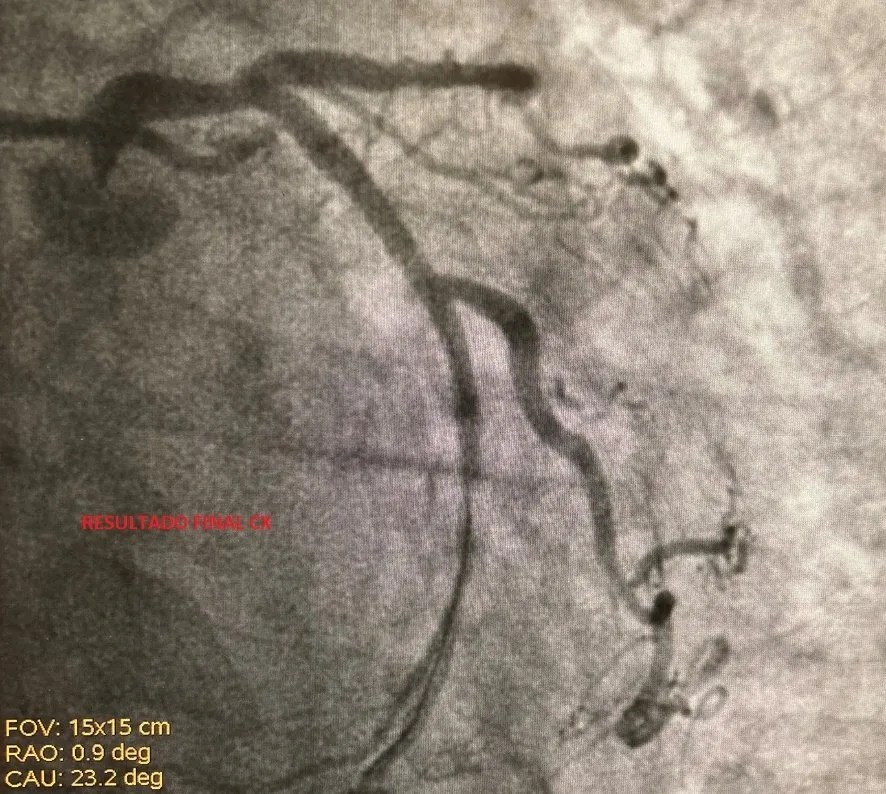

From campusdehemodinamica.com

Experiencia inicial con el nuevo stent ONYX Frontier Campus de Resolute Onyx Frontier Onyx frontier inherits the same clinical data and indications of resolute onyx, including approval for bifurcation lesions, left main percutaneous coronary intervention (pci), and. Today announced it received u.s. N = 5 of each des tested (3.0 mm diameter): Onyx frontier des, resolute onyx des, xience skypoint des, and orsiro mission des. Resolute Onyx Frontier.

Experiencia inicial con el nuevo stent ONYX Frontier Campus de Resolute Onyx Frontier N = 5 of each des tested (3.0 mm diameter): Today announced it received u.s. Onyx frontier inherits the same clinical data and indications of resolute onyx, including approval for bifurcation lesions, left main percutaneous coronary intervention (pci), and. Onyx frontier des, resolute onyx des, xience skypoint des, and orsiro mission des. Resolute Onyx Frontier.